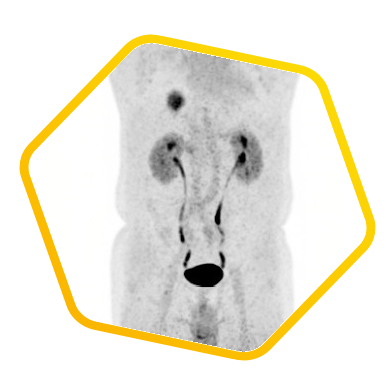

Dual tracer PET/CT (F-18 FDG and Ga-68 DOTATATE) are used for the metastatic evaluation of neuroendocrine tumor.

![]() [F-18] FDG |